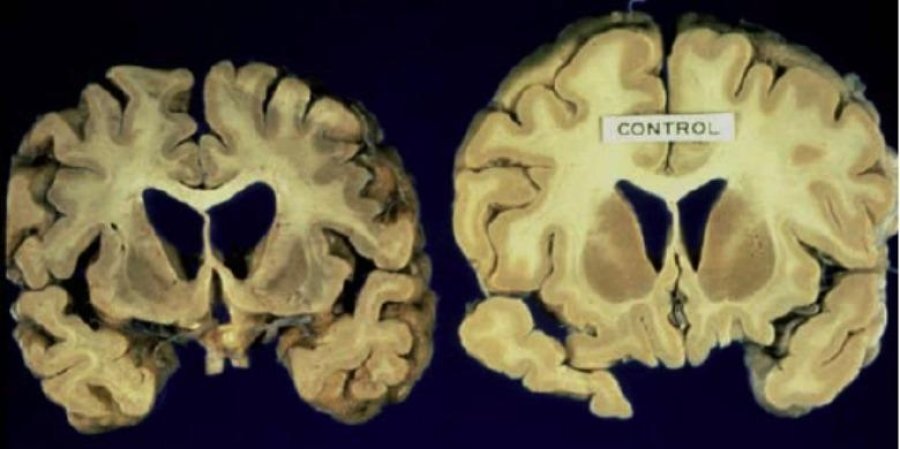

Прион: развитие болезни. Слева пораженный мозг, справа здоровый